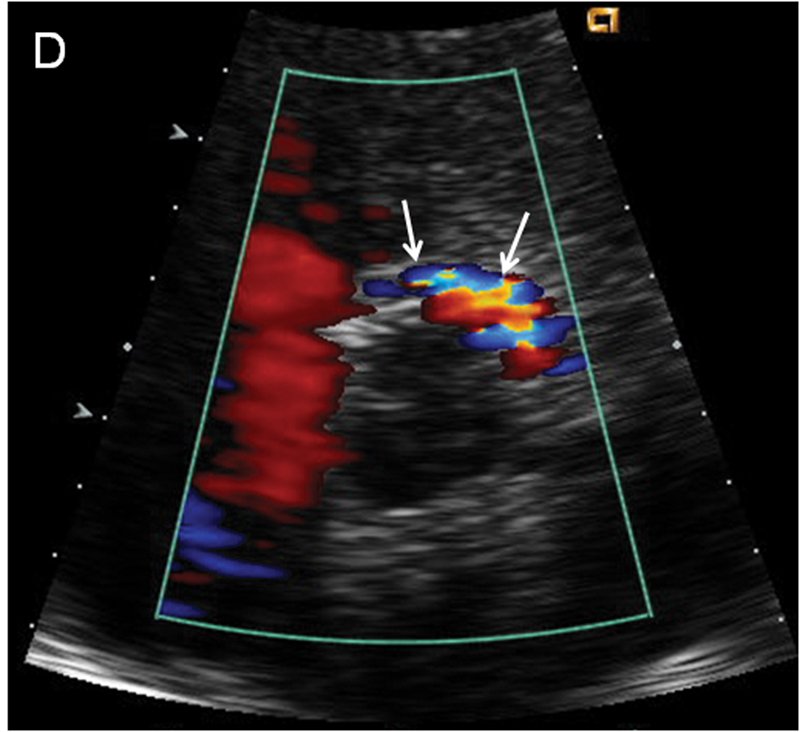

فحوصات تشخيصية لبعض امراض القلب والشرايين التاجية